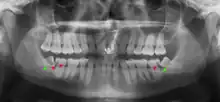

| Diagnostic method | Examination, x-ray |

Impacted wisdom teeth are classified by their direction of impaction, their depth compared to the biting surface of adjacent teeth and the amount of the tooth's crown that extends through gum tissue or bone. Impacted wisdom teeth can also be classified by the presence or absence of symptoms and disease. Screening for the presence of wisdom teeth often begins in late adolescence when a partially developed tooth may become impacted. Screening commonly includes a clinical examination as well as x-rays such as panoramic radiographs.

If the tooth cannot be assessed with clinical exam alone, the diagnosis is made using either a panoramic radiograph or cone-beam CT. Where unerupted wisdom teeth still have eruption potential several predictors are used to determine the chance of the teeth becoming impacted. The ratio of space between the tooth crown length and the amount of space available, the angle of the teeth compared to the other teeth are the two most commonly used predictors, with the space ratio being the most accurate. Despite the capacity for movement into early adulthood, the likelihood that the tooth will become impacted can be predicted when the ratio of space available to the length of the crown of the tooth is under 1.[5]: 141

There is no standard to screen for wisdom teeth. It has been suggested, absent evidence to support routinely retaining or removing wisdom teeth, that evaluation with panoramic radiograph, starting between the ages of 16 and 25 be completed every 3 years. Once there is the possibility of the teeth developing disease, then a discussion about the operative risks versus long-term risk of retention with an oral and maxillofacial surgeon or other clinician trained to evaluate wisdom teeth is recommended. These recommendations are based on expert opinion level evidence.[19] Screening at a younger age may be required if the second molars (the "12-year molars") fail to erupt as ectopic positioning of the wisdom teeth can prevent their eruption. Radiographs can be avoided if the majority of the tooth is visible in the mouth.